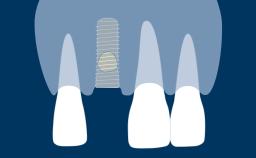

The esthetic aspects of implant prostheses have gained increasing attention and importance in recent years. There are a number of factors that determine if implant prostheses are considered esthetically successful by both the patient and the clinician.

In the example of a suboptimal outcome, the implant-supported prostheses replacing the upper left central and lateral incisors are clearly distinguishable from their right-side counterparts.

On the other hand, in this example of an optimal outcome the right central incisor implant crown and soft tissue emergence closely mimic the natural left central incisor.

With the aim of achieving optimal esthetics, this Learning Module will outline and discuss the determining factors related to esthetic planning for fixed dental prostheses or FDPs.